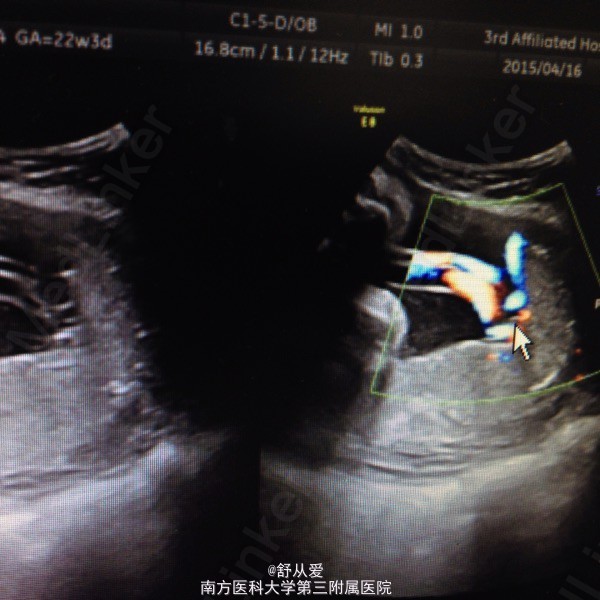

查体:生命体征正常,腹部隆起如孕足月大小,头位,胎心音正常。B超:宫内晚孕,帆状胎盘,血管前置待排。

诊断:孕1产0孕38+4周,单活胎,帆状胎盘,血管前置 处理:入院后完善检查,行剖宫产术。术中切开子宫肌层,见一血管附着于胎膜上,血管位于子宫切口正中,避开血管,刺破胎膜,娩出胎儿。母胎健康出院。